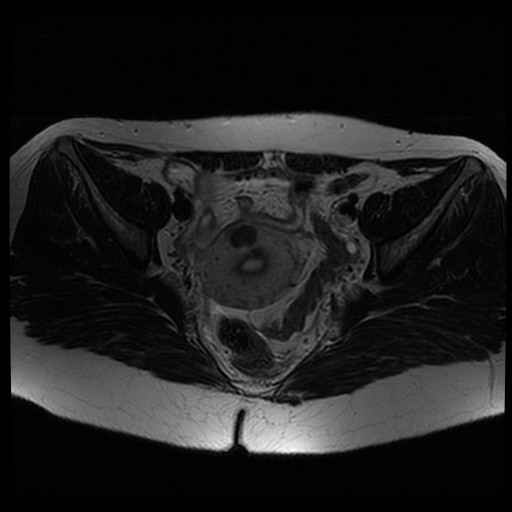

Bekken